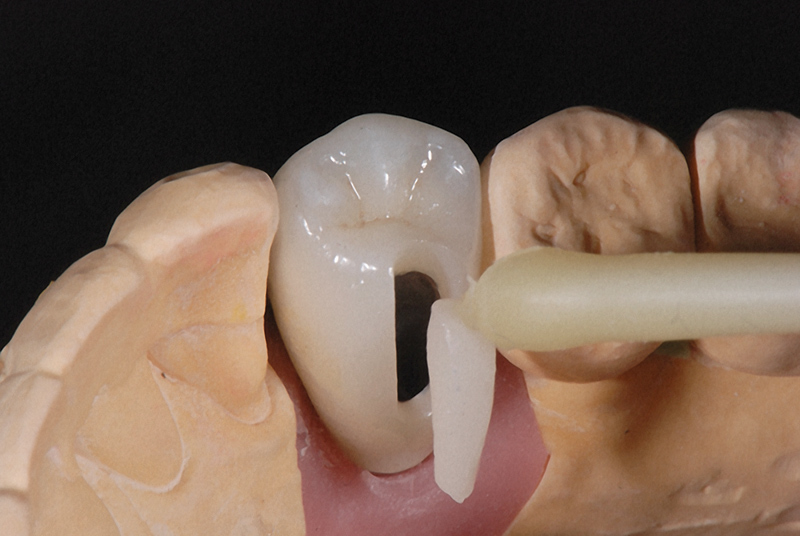

The main biological consideration with cement-retained implant restorations is the vulnerability of peri-implant tissues. Cement contamination readily occurs around implant sites for many reasons. First, as previously mentioned, the soft tissues are much more delicate and vulnerable to tearing when using protection techniques such as retraction cord placement, which is, therefore, contraindicated.16 Cord placement has been shown to strip the weak hemidesmosomal attachment and provide a pathway along the side of the implant for cement extrusion to occur (Figure 1 and Figure 2).17

Techniques have been developed to assist clinicians in approximating the right amount of cement.26 For example, pre-extrusion—extraorally with a custom copy abutment—is a quick, easy, and inexpensive method (Figure 9 through Figure 11).

Figure 1

Figure 2